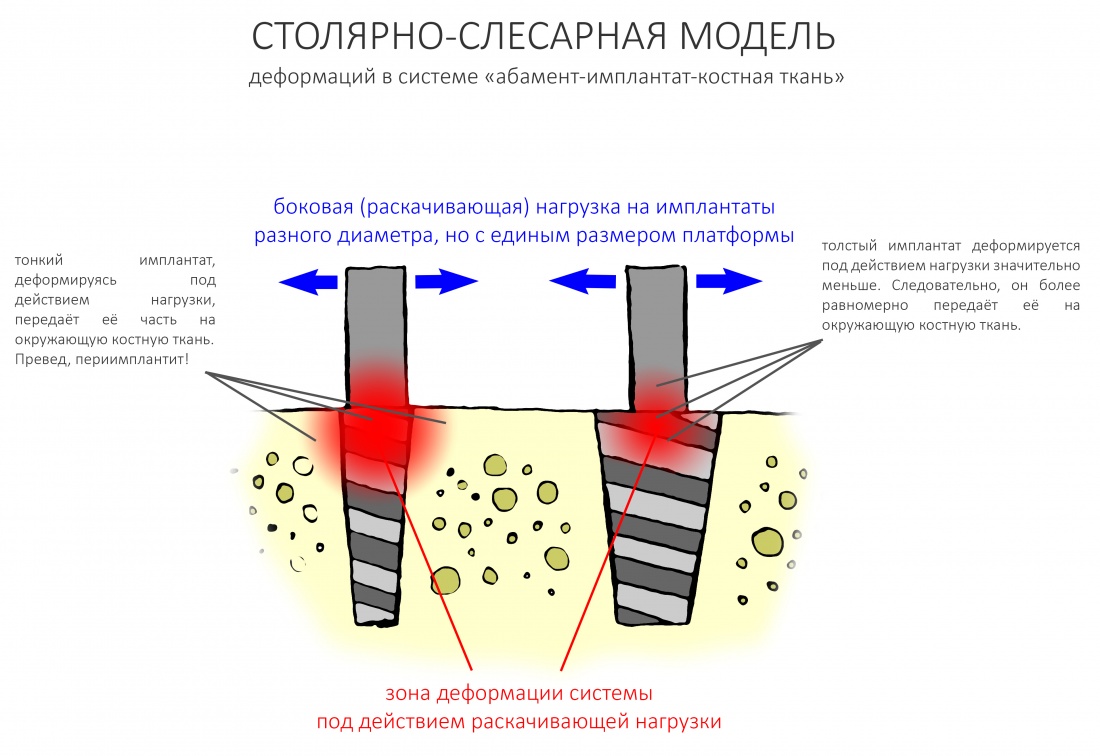

Во-первых, некоторые имплантационные системы имеют единый по размеру ортопедический интерфейс, вне зависимости от диаметра самого имплантата. Такими имплантационными системами являются, к примеру, Dentium, Ankylos, Bicon etc.

И, если размер ортопедической платформы одинаков, то есть ли смысл так заморачиваться на диаметре имплантата, ведь площадь опоры абатмента мы всё равно не поменяем? И вообще, имплантаты с одним размером ортопедической платформы, вроде как, своим существованием отрицают необходимость подбора по диаметру. И не совсем понятно, почему их вообще в разных диаметрах выпускают:

Причина того, что имплантаты с единой ортопедической платформой могут иметь разные диаметры, очень проста и понятна. Тонкий имплантат под действием нагрузки будет гнуться и деформироваться, в отличие от большего по диаметру. Тонкий имплантат будет менее равномерно передавать получаемую нагрузку на окружающую костную ткань. Это очень легко продемонстрировать на простой столярно-слесарной модели:

Вот почему имплантологическое правило #2 справедливо даже для имплантатов с единой платформой, хотя может показаться, что подбор их по диаметру не столь важен. Инструкция к Dentium это подтверждает.